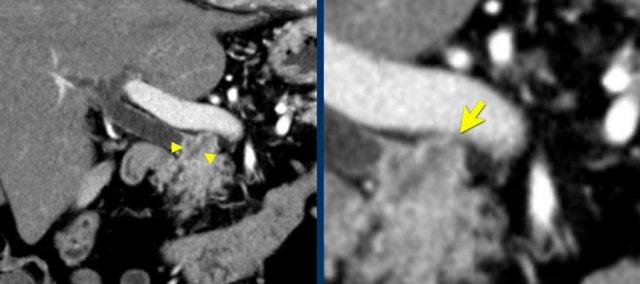

Hình CT axial cho thấy một động mạch gan phải phụ thêm (mũi tên vàng) đi qua vùng lân cận một khối giảm tỷ trọng ở đầu tụy (đầu mũi tên).

Sự liên quan mạch máu được đánh giá rõ hơn trên ảnh tái tạo mặt phẳng đứng dọc. Có sự áp sát 90 – 180° của động mạch gan phải thay thế (mũi tên trắng) bởi ung thư biểu mô tuyến đầu tụy (đầu mũi tên trắng).

Động mạch gan trái nguyên bản đi theo hướng ra trước hơn, tĩnh mạch cửa nằm ở giữa.

Cuộc phẫu thuật là cắt bỏ diện R1.

Các hình ảnh axial của cùng bệnh nhân có chú thích.